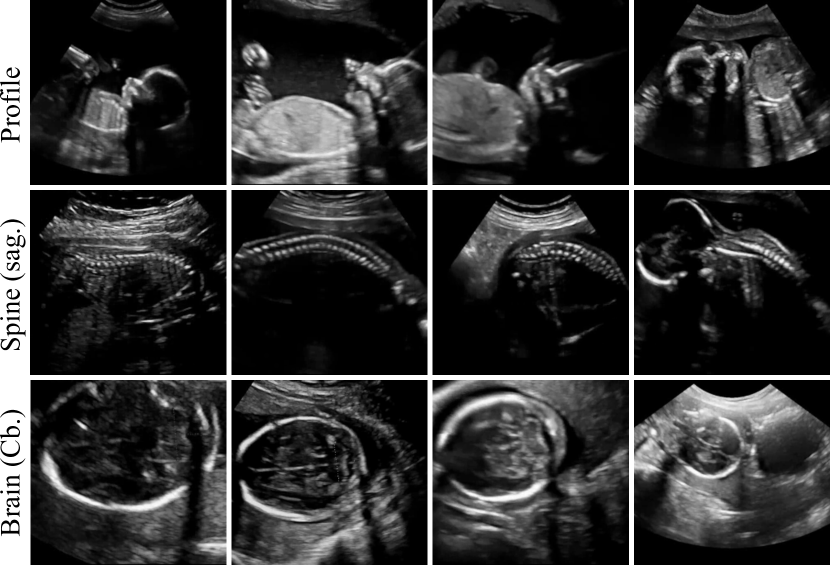

A large fraction of the freeze-frame images corresponded to standard planes and have been manually annotated during the scan allowing us to infer the correct ground-truth (GT) label. Based on those labels we split the image data into 13 standard views. In particular, those included all views required to be saved by the FASP guidelines, the four most commonly acquired cardiac views, and the facial profile view. An overview of the modelled categories is given in Table I and examples of each view are shown in Fig. 7.

Refer to caption

Figure 7: Results of retrospective retrieval for two example subjects. The respective top rows show the ground truth (GT) saved by the sonographer. The bottom rows show the retrieved (RET) frames. For subject (a) all frames have been correctly retrieved. For subject (b) the frames marked with red have been incorrectly retrieved.

The retrieved frames for two cases from the test cohort are shown in Fig. 7 along with the ground truth (GT) frames saved by the sonographers. In the case shown in Fig. 7a, all views have been correctly retrieved. It can be seen that most of the retrieved frames either matched the GT exactly or were of equivalent quality. We observed this behaviour through-out the test cohort. However, a number of wrong retrievals occasionally occurred. In agreement with the quantitative results in Tab. VI, we noted that cardiac views were affected the most. Fig. 7b shows a case for which two cardiac views have been incorrectly retrieved (marked in red).